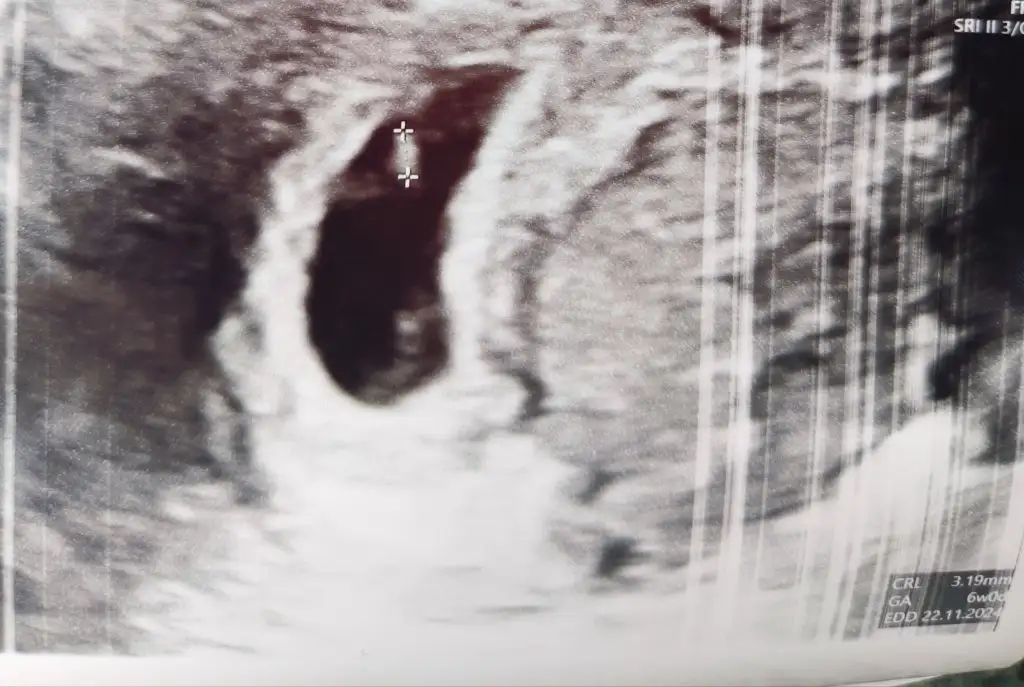

Kuzu 26 Mart 104 ise 28 Mart'ta 104*2 den 208 olması gerekiyor. Yani 29 Mart'ta 208 den bir tık daha yüksek olması gerekir. Ama inşallah sağlıklı ilerler. Doktorun daha iyisini bilir26 mart ilk test 104 29 mart 163 yuzde 60 gibi artis sali tekrar gideceğim sizce nasil artis orani ?

Banada biraz düşük geldi. Pazar gunu ozel hastanede test verecegim birde sabahtan . Olumsuz düşünmek istemiyorum umut isteKuzu 26 Mart 104 ise 28 Mart'ta 104*2 den 208 olması gerekiyor. Yani 29 Mart'ta 208 den bir tık daha yüksek olması gerekir. Ama inşallah sağlıklı ilerler. Doktorun daha iyisini bilir

Karından ise erkek gibi canım ama yinede belliCanım buralardaysan bi tahmin isterimGerçi kalp atışı 90-100 arası, biraz düşük gibi, yine moralsizim, inşallah yükselir melegim can

Bu arada karından ultrason.

Üniversite hastanesinde duyulamadi dediler, eski özel doktoruma gittim, o da 90-100 arası dedi, küçük olduğu için normal dedi ama bana düşük gibi geldi, içime bi kurt düştü, hayırlısı inşallahKarından ise erkek gibi canım ama yinede belli

Olmaz ortada duruyor. Doktoe mu dedi kalp atışı düşük diye bi sıkıntı mı var 100 çokta düşük degil aslında. İnşallah saglıkla ilerler bi sıkıntı çıkmaz canım